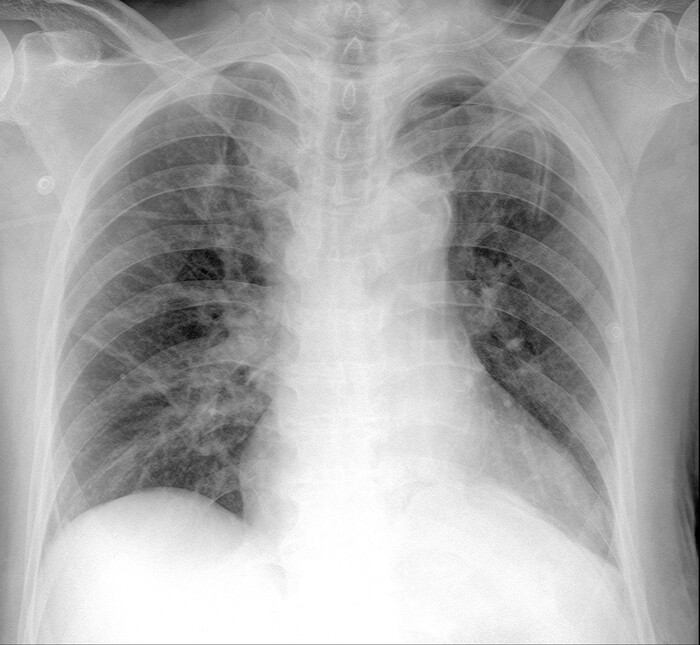

Снимок пациентки после операции. В принципе, левое легкое несильно отстает по размерам от правого. Во многом это заслуга сохраненного нами сегмента, который расправился еще больше и занял собой пустоту: